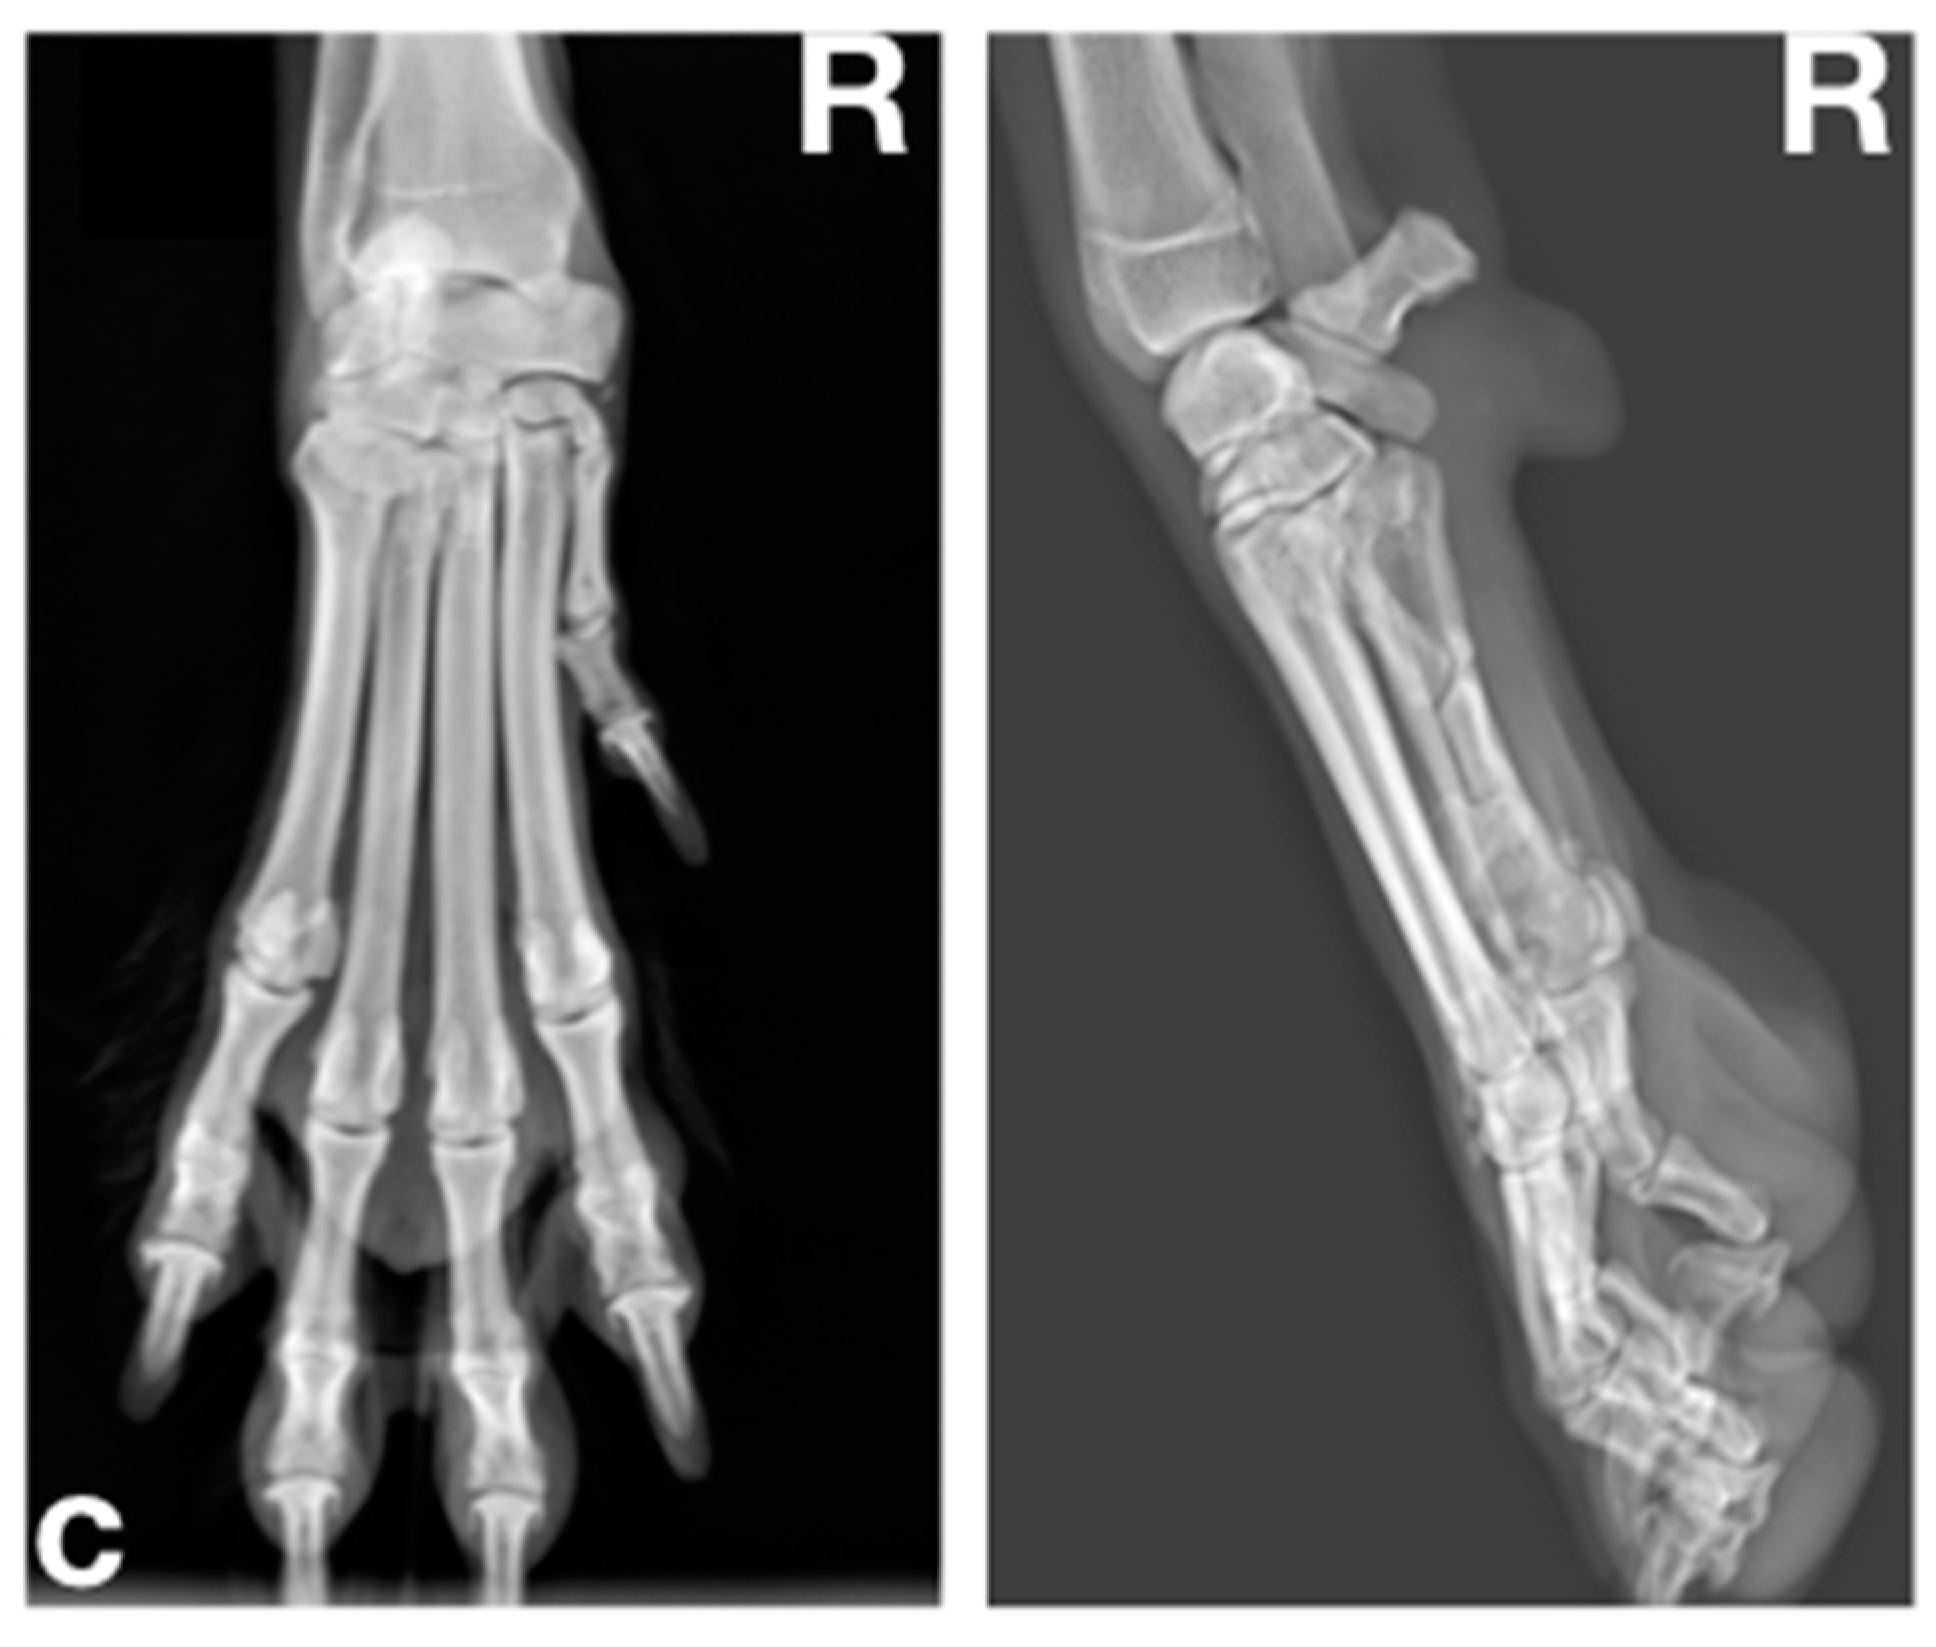

2.1.2. Radiographic Examination

2.2.2. Radiographic Examination

2.3.2. Radiographic Examination